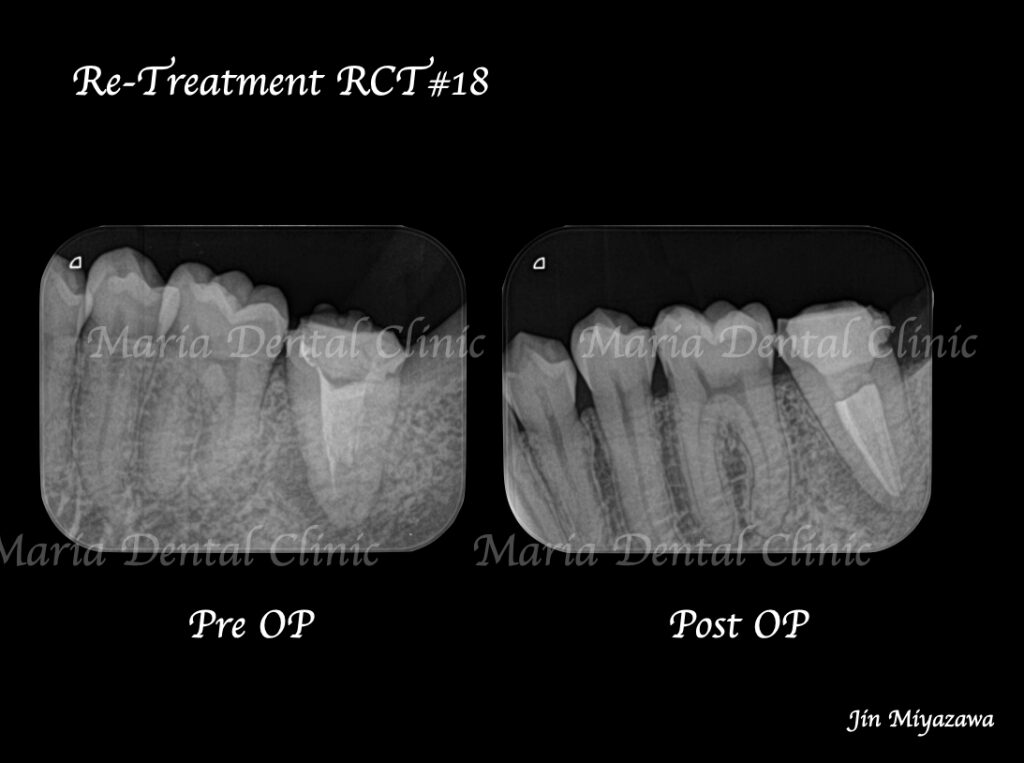

に対する、精密根管治療のアプローチ(再根管治療)_治療前のレントゲン画像1.jpg)

に対する、精密根管治療のアプローチ(再根管治療)_治療前のレントゲン画像2.jpg)

前医にて根管治療を終了したが、痛みと違和感に改善がないため来院された患者様です。前医では樋状根(といじょうこん)の為、これ以上の治療はできないと言われ、抜歯を勧められていました。

に対する、精密根管治療のアプローチ(再根管治療)_治療前後比較治療前のレントゲン画像.jpg)

に対する、精密根管治療のアプローチ(再根管治療)_治療前後比較治療後のレントゲン画像.jpg)

バイオセラミックにて根管充填を行いました。レントゲン写真からは根尖まで良好に隙間なく根管充填を行っていることが確認できます。

1回目の治療終了後、2週間後には違和感等は感じられないようにまで回復しました。